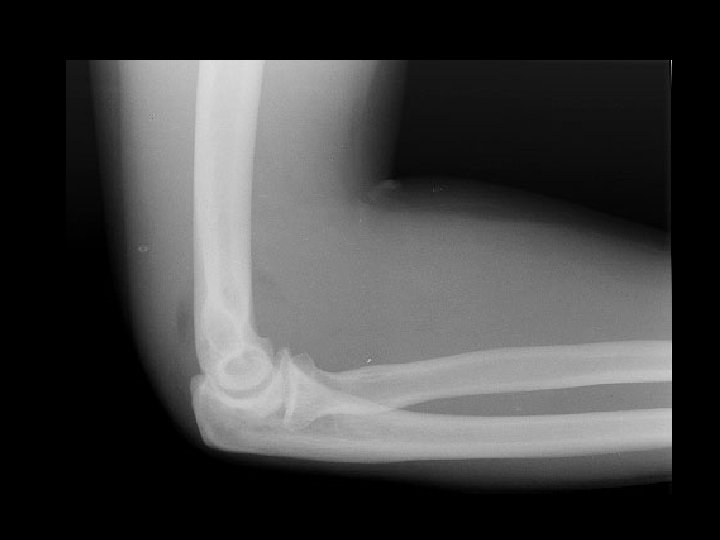

Radial head fracture • Findings: – Visualization of both the anterior and posterior fat – “spinnaker sign” – most common adult elbow fracture – assume radial head fracture even if not clearly seen • ddx: – NONE! – This is an Aunt Minnie!